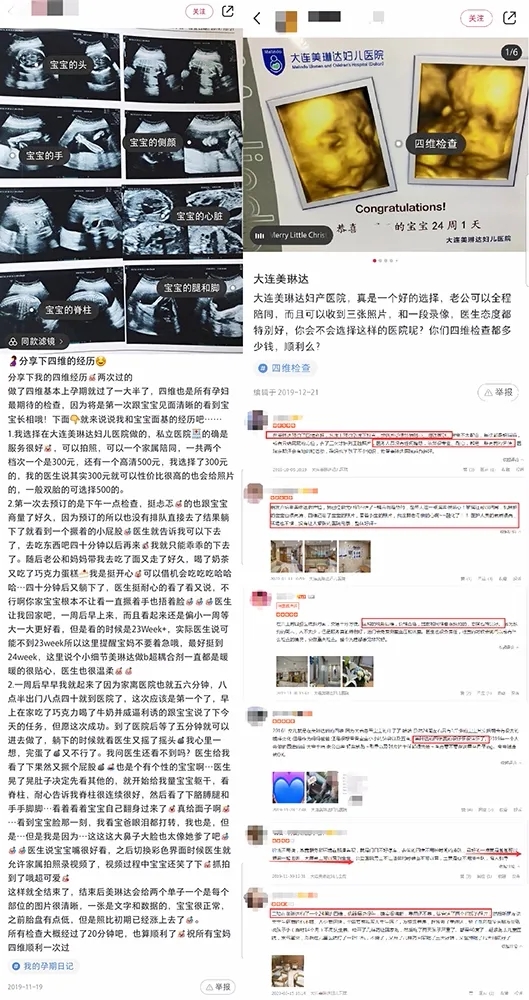

(美琳达四维宝宝照片)

美琳达孕中期四维彩超检查价格是清晰透明化,不存在隐形消费,或者只检查部分检查项目。所有四维筛查项目,都是一次性收费!

(美琳达四维彩超在大众点评、小红书上孕妈好评分享)